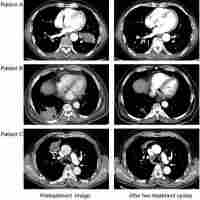

| Abstract | According to the National Comprehensive Cancer Network (NCCN) guidelines, treatment plans for nonsmall cell lung cancer are to be based on cancer stage. Cancer staging for patients with resectable disease has been based on pathologic stage instead of preoperative clinical stage. However, the possibility of occult mediastinal lymph node metastases could lead to discrepancy between clinical and pathologic stage. While multi-modality treatments may be beneficial for patients with locally advanced disease, most studies have been based on clinical stage. The aim of this study was to identify the beneficial impact of neoadjuvant therapy and the prognostic value of final pathologic stage in these patients. |